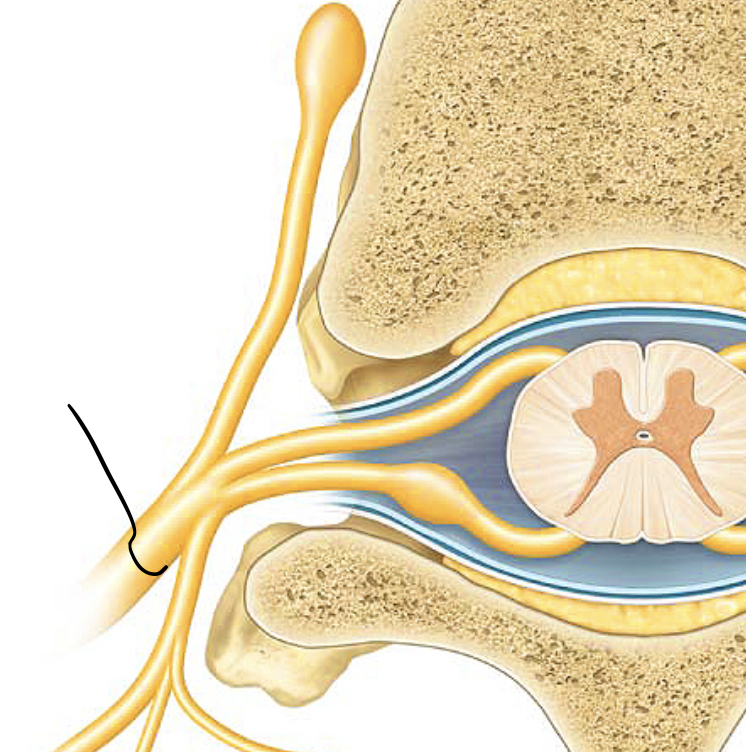

dorsal root

the sensory branch of each spinal nerve

dorsal root ganglion

contains cell bodies of sensory neurons

ventral root

the basal branch of each spinal nerve; carries motor neurons

spinal nerve

a peripheral nerve attached to the spinal cord. Motor and Sensor nerve.

rami

branches of spinal nerves

dorsal ramus

the division of posterior spinal nerves that transmit motor impulses to the posterior trunk muscles and relay sensory impulses from the skin of the back

ventral ramus

what. is the second arrow pointing at?

gray rami communicantes

Carry unmyelinated postganglionic sympathetic axons from trunk to all spinal nerves

sympathetic trunk

nerve running along each side of the vertebral column

sympathetic trunk ganglia

big yellow thing